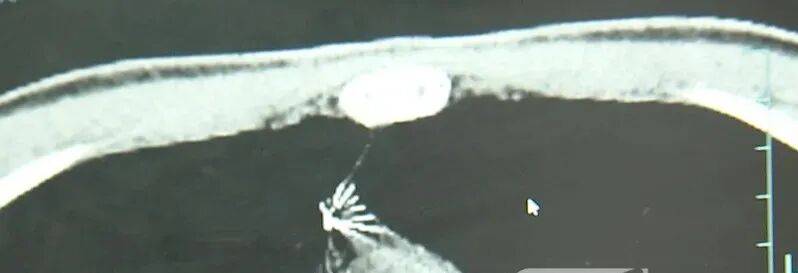

近日,安徽17岁小伙小陆参加征兵体检,胸片结果显示:胸腔内有一处金属高密度影,形态细长,像一根针虚拟币ACN是什么。

进一步的CT检查确认,异物是一枚金属针,斜插在肺组织内,位置十分凶险虚拟币ACN是什么。

杭州市第一人民医院心胸外科副主任冯兴说:“我们看到这个针的尖锐部,正好指向他体内的一个大血管,边上是上腔静脉和胸主动脉,因此这个针稍有不慎,就有可能造成周边血管的损伤,甚至危及生命虚拟币ACN是什么。”